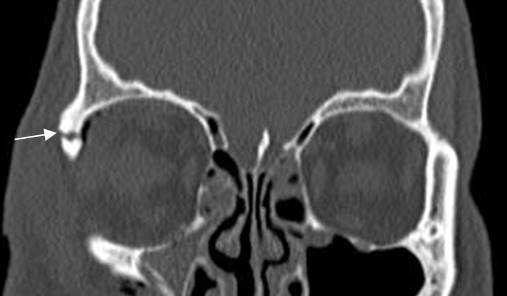

Fig 217. Fractura de órbita.

TAC reconstrucción coronal. Fractura no desplazada en el borde lateral de la órbita.